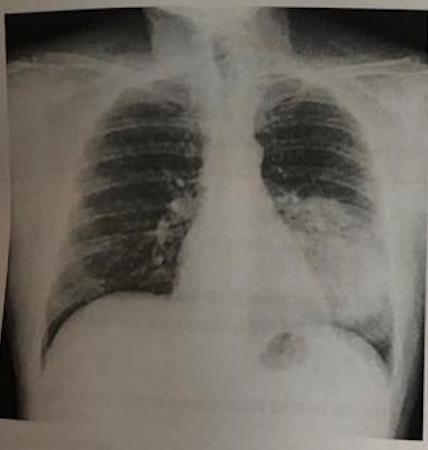

35) Indique la patología que sugiere la siguiente imagen:

Fig. 3

Tuberculosis

Neumonia

Enfisema.

Derrame pleural.

Todas son falsas.